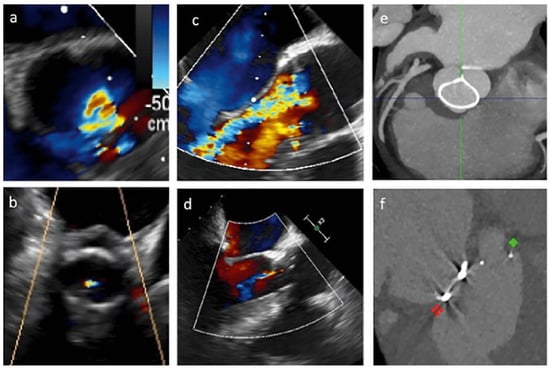

In-hospital survival was 100%. Predischarge echocardiography showed no cases of residual aortic regurgitation classed as more than mild or stenosis. An initial reduction of left ventricle volume was recorded (mean LVEDV 126 ± 36 ml). Echo-analysis before discharge showed a mean regurgitant volume of 13 ± 8 ml/beat. No increased gradients were detected (mean gradient 10 ± 4 mm Hg). Table 2 presents the main echocardiographic results. Postoperative course was event-free, except for one case of transient delirium and two cases of postoperative pericardial effusion in patients with valve sparing operations. No complete atrioventricular block or pacemaker implantation occurred. Mean hospital stay was 8 ± 1 days. Figure 2 presents the results of postoperative imaging evaluations with echocardiography and CT scans.

Figure 2.

Main features of aortic valve repair with HAART ring implantation. (a), (b) Transoesophageal echocardiographic short axis view of the aortic valve before and after repair; (c), (d) long axis view of the aortic valve before and after repair; (e) postoperative CT; (f) postoperative CT showing double ring implantation.